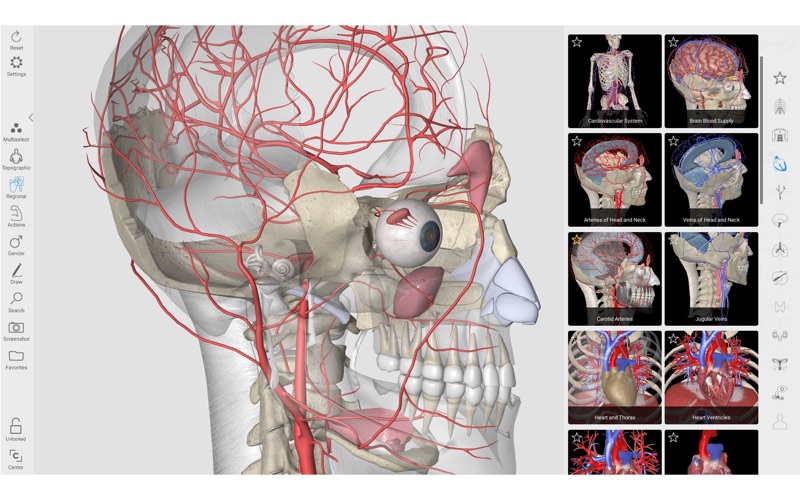

2. 3D Organon Anatomy is an interactive anatomical atlas featuring all 15 human body systems.

6. It features all body systems: Skeletal, Connective, Muscular, Arterial, Venous, Nervous, Lymphatic, Heart, Respiratory, Digestive, Endocrine, Urinary, Reproductive, Sensory organs, and Integumentary (skin).

10. 3D Organon unfolds life-like high resolution 3D models covering every aspect of the human body.